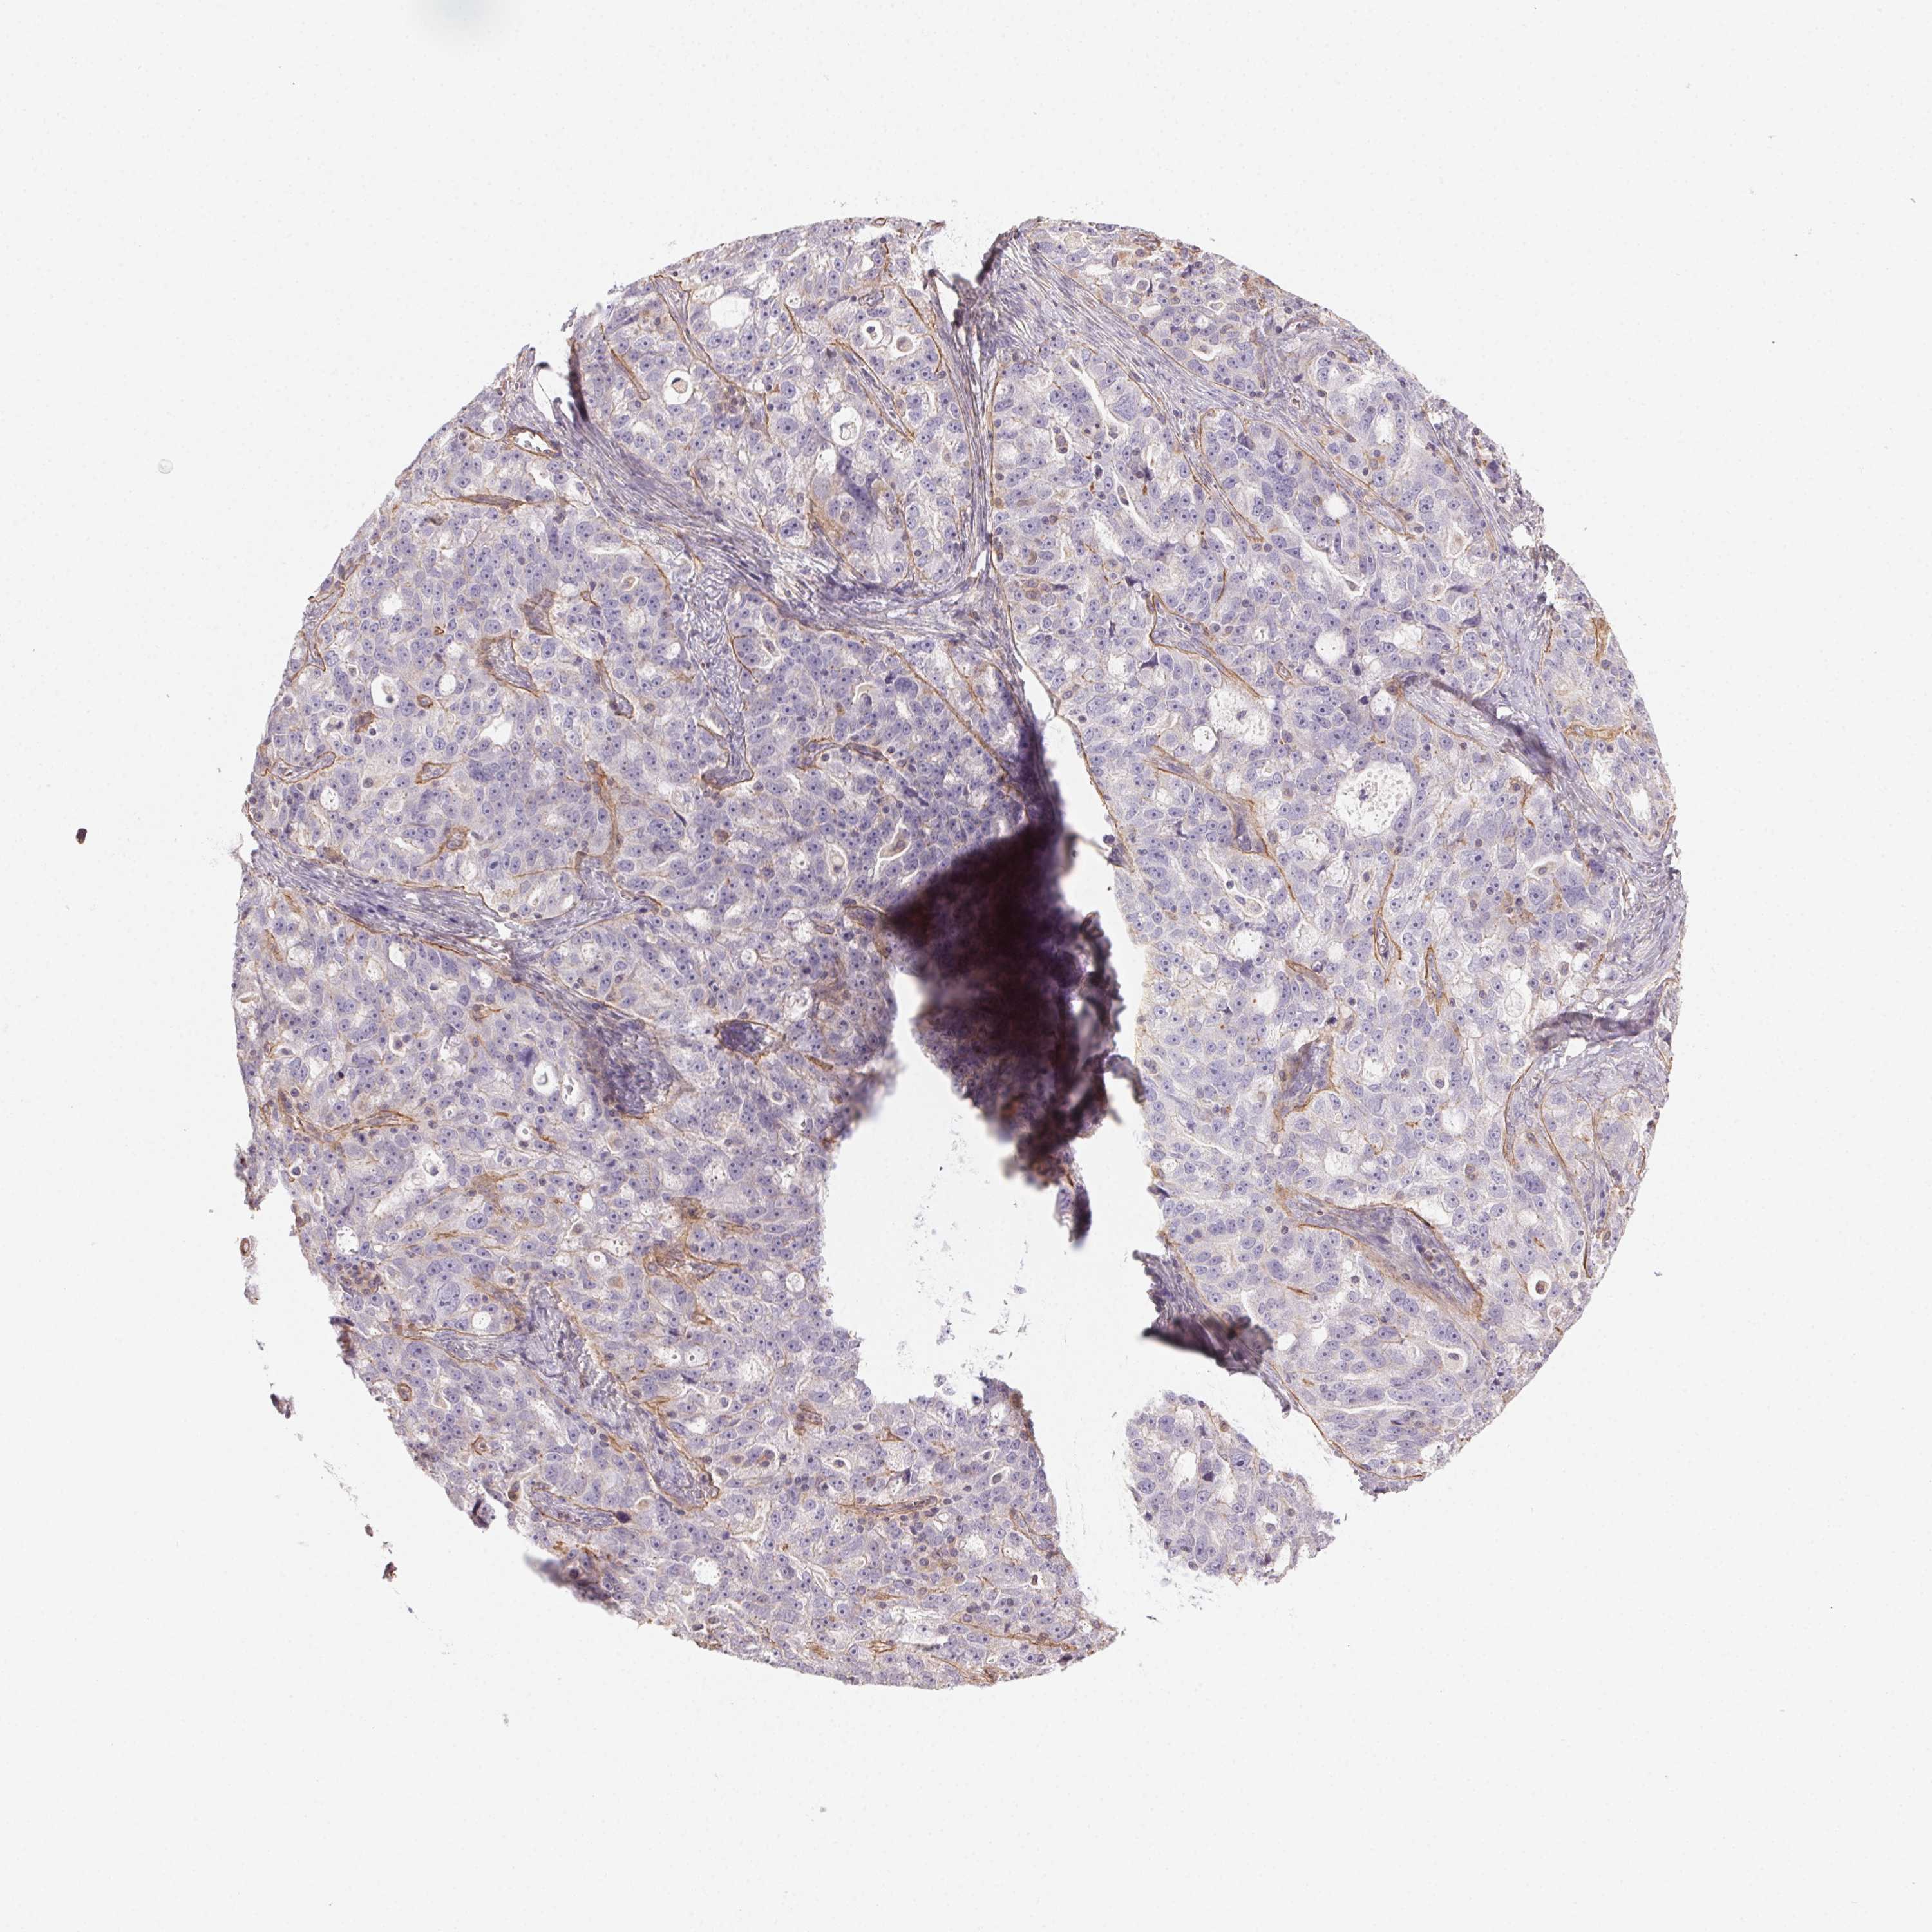

OVARIAN CANCER - Protein expressioni

A mouse-over function shows sample information and annotation data. Click on an image to view it in a full screen mode. Samples can be filtered based on level of antibody staining by selecting one or several of the following categories: high, medium, low and not detected. The assay and annotation is described here.

Note that samples used for immunohistochemistry by the Human Protein Atlas do not correspond to samples in the TCGA dataset.

Antibody stainingi

Antibody staining in the annotated cell types in the current human tissue is reported as not detected, low, medium, or high, based on conventional immunohistochemistry profiling in selected tissues. This score is based on the combination of the staining intensity and fraction of stained cells.

Each image is clickable and will lead to virtual microscopy that enables deeper exploration of all samples and also displays staining intensity scores, fraction scores and subcellular localization as well as patient and tissue information for each sample.

Antibody HPA056752

Cystadenocarcinoma, serous, NOS

Cystadenocarcinoma, mucinous, NOS

Carcinoma, endometroid